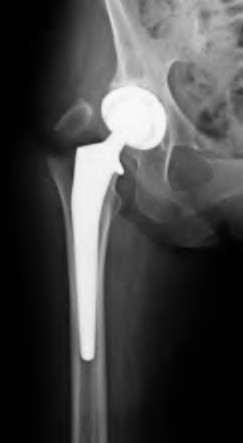

A 67-year-old man who underwent total hip arthroplasty (THA) 4 years ago fell on to his right hip. His pre-injury right hip film is seen in Figure A while films of his current injury are seen in Figures B and C. Prior to the fall he had no thigh or hip pain. His ESR and CRP are within normal limits. During intraoperative assessment, the acetabular and femoral stems are found to be well fixed. What is the next best course of action?

This patient has a periprosthetic hip fracture at the level of the stem with a stable prosthesis, indicated open reduction and internal fixation as the treatment of choice.

The Vancouver Classification can be helpful in clinical decision-making regarding fixation versus revision of periprosthetic hip fractures of the proximal femur. A stable implant, by nature, does not need to be revised in the setting of adequate bone stock for fixation, but the ultimate test of stability should be in the operating room. Many fixation strategies are appropriate, but many implants include locking plate fixation for concerns of stress-shielded bone around the implant as well as use of unicortical fixation at the level of the stem.

Pike et al review the current trends in treating B1 fractures including locking plates with strut allografts, minimally invasive plate osteosynthesis (MIPO) and locking plates spanning femoral THA and TKA stems in selected patients. The authors conclude that no studies currently provide evidence establishing one

Illustration A shows a possible fixation construct for this patient's fracture. The Vancouver Classification is seen in Illustration B and Illustration C represents an algorithm for treatment options.